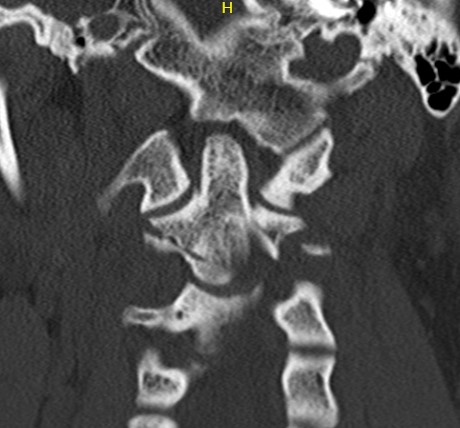

Anatomy

Superior projecting bony element of C2 / axis

C1 / atlas rotates around the dens to provide cervical rotation

Type 2

Fracture of base of odontoid process

Type 3

Fracture through body of axis

Type II Dens Fracture

Type III

Definition

Through the body of C2

May involve portions of C1 or C2 facets